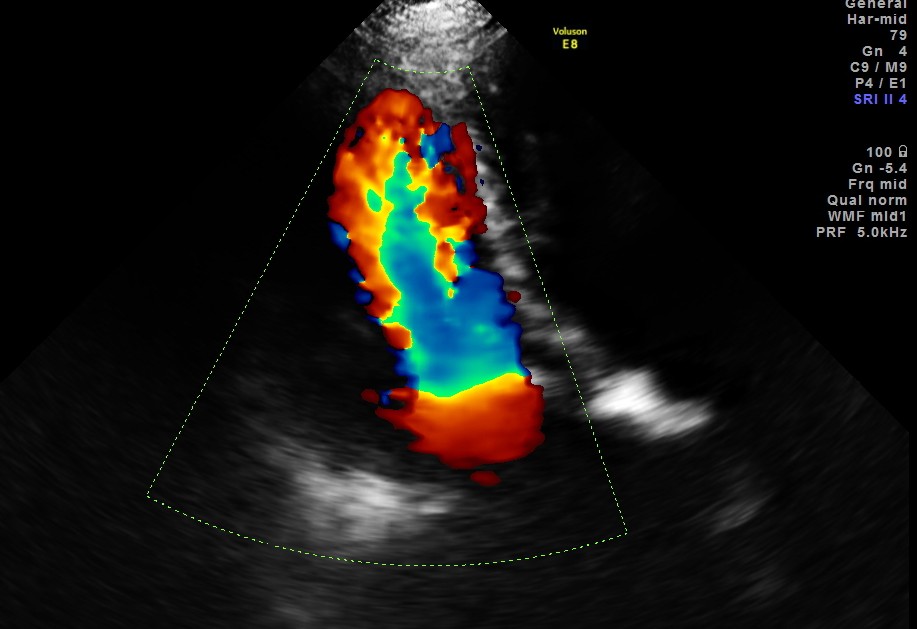

Her Echo cardiogram showed the following findings :

This patient had Rheumatic heart disease , moderate mitral stenosis with pulmonary hypertension .